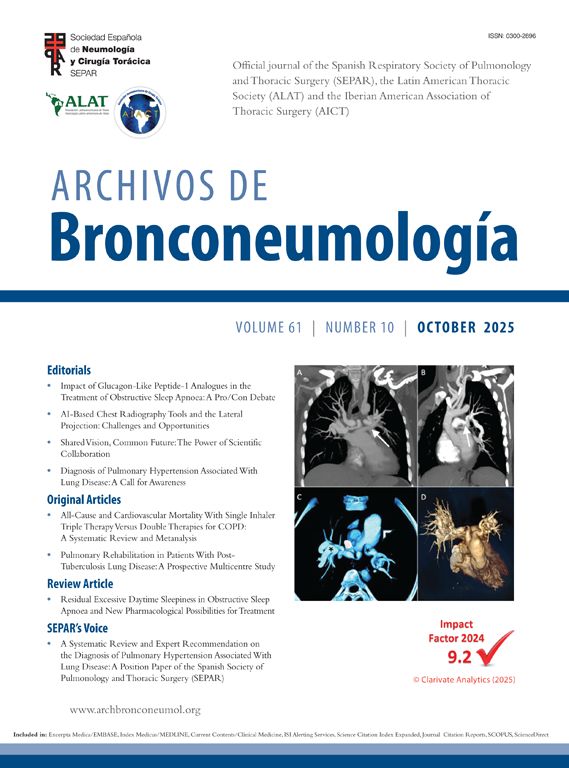

We report a 64-year-old Spanish male smoker (70 pack-years) with a history of HIV on antiretroviral therapy and hepatitis C-related cirrhosis grade 2. He was referred from Infectious Diseases following an asymptomatic high-risk screening chest CT in June 2025. Physical examination was unremarkable. Chest CT demonstrated a 31mm spiculated mass in the right upper lobe (RUL) with positive bronchus sign, focal scarring, and calcifications, without significant hilar or mediastinal lymphadenopathy (Fig. 1A). PET scan confirmed increased metabolic activity in the pulmonary mass (Fig. 1C). Initial flexible bronchoscopy with r-EBUS identified the lesion in the RUL apical sub-segment, but microbiological cultures showed no growth and brush cytology was negative for malignant cells. In a second bronchoscopy, we employed the Olympus BF-UCP190F, to navigate to the fifth bronchial generation within the RUL apical sub-segment (Fig. 1D). A hypoechoic lesion with hyperechoic borders was identified and sampled using a ViziShot2 25G needle (three passes). Subsequent r- EBUS (UM-S20-17S, Olympus) confirmed a hypoechoic lesion with air–lesion interface reflex distal to the puncture site (Fig. 1B). Cytology from peripheral EBUS-TBNA revealed abundant atypical epithelial cells consistent with non-small cell lung carcinoma. Finally, the patient was diagnosed with T2aN0M0 lung cancer and deemed suitable for surgical resection.

(A) Chest CT with a 31mm spiculated mass in the right upper lobe with positive bronchus sign. (B) Hypoechoic lesion with air-lesion interface in right upper lobe apical sub-segment. (C) PET-CT confirmed increased metabolic activity in 31mm speculated mass in the right upper lobe. (D) Hypoechoic lesion with hyperechoic borders in contact with the lumen of right upper lobe apical sub-segment.